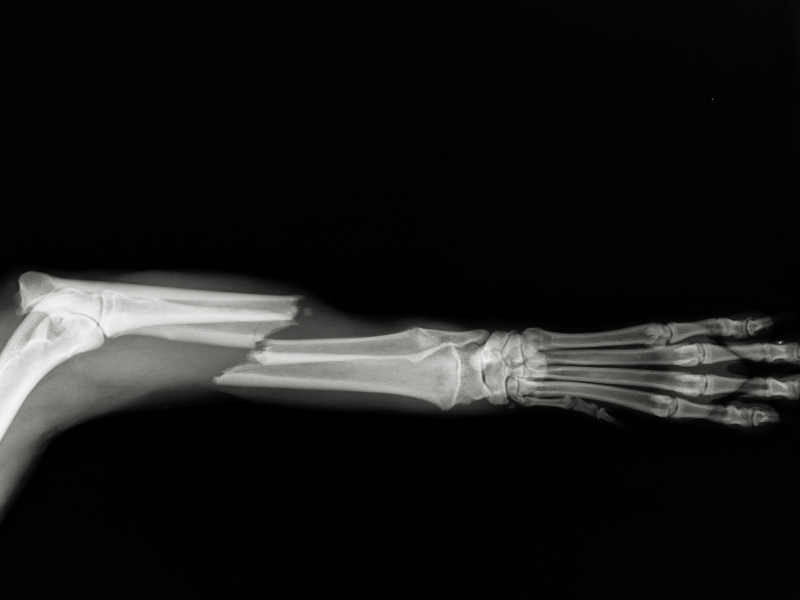

Orthopedic fractures are typically diagnosed through physical examination, imaging tests such as X-rays, CT scans, or MRI to determine the extent of the damage. Treatment varies based on the type and location of the fracture, as well as the patient’s overall health. It may include:

Fractures are diagnosed through physical examinations and imaging tests like X-rays, CT scans, or MRI. These tests help determine the type, location, and severity of the fracture.